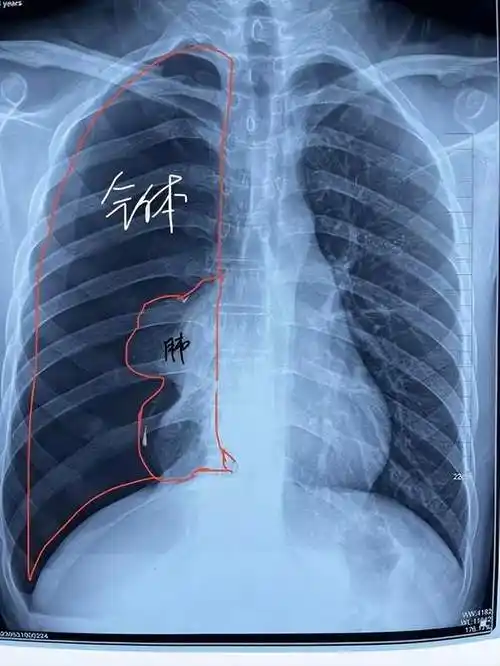

关于气胸你了解多少?_治疗_患者_胸腔